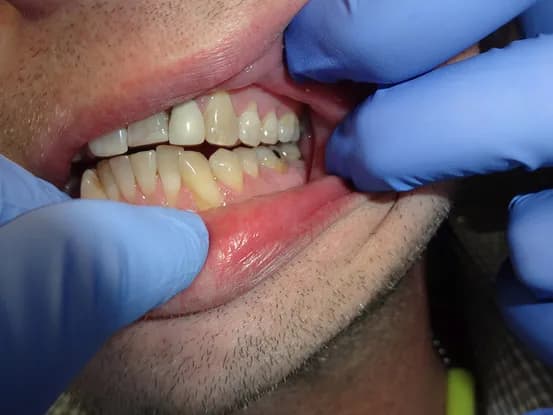

Case 3

35 year old male with extensive cervical decay resulting from diet high in sugars. 8 units of Porcelain crown & bridge performed. Missing tooth was eventually replaced with implant after photo was taken.